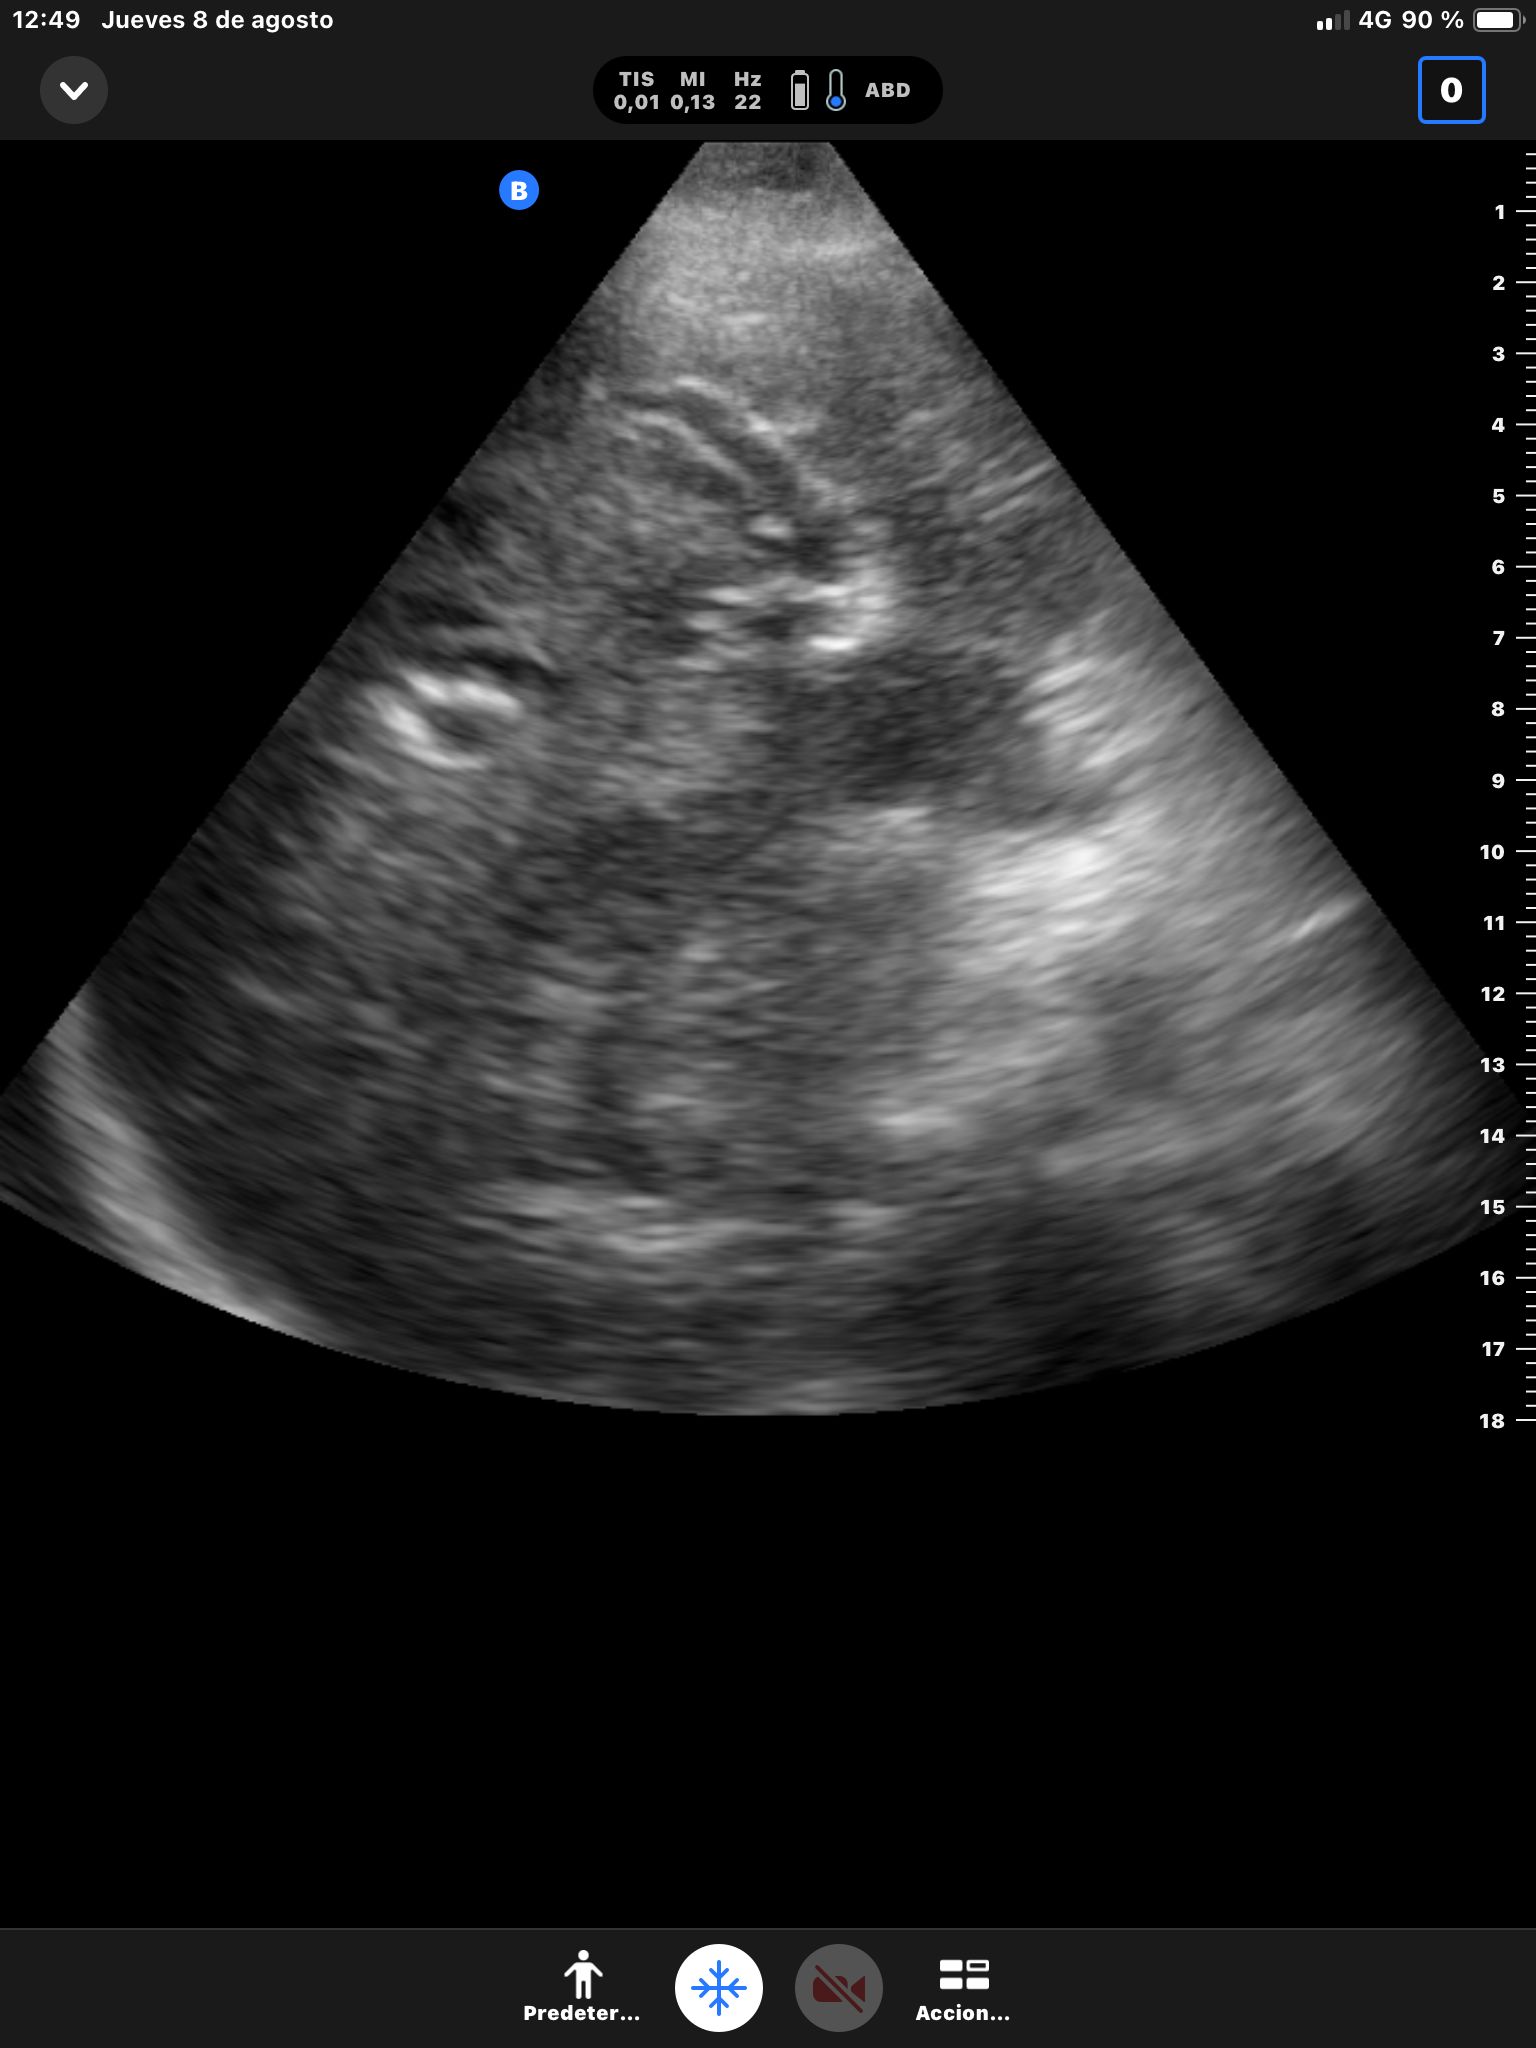

Se realiza ecografía abdominal.

Descripción de los hallazgos ecográficos y las imágenes más relevantes para la resolución del caso

Hígado sin LOEs. Vesícula biliar con hidrops (58 mm), dilatación del colédoco (10 mm). Páncreas hiperecogénico, atrófico, Wirsung de 76 mm.